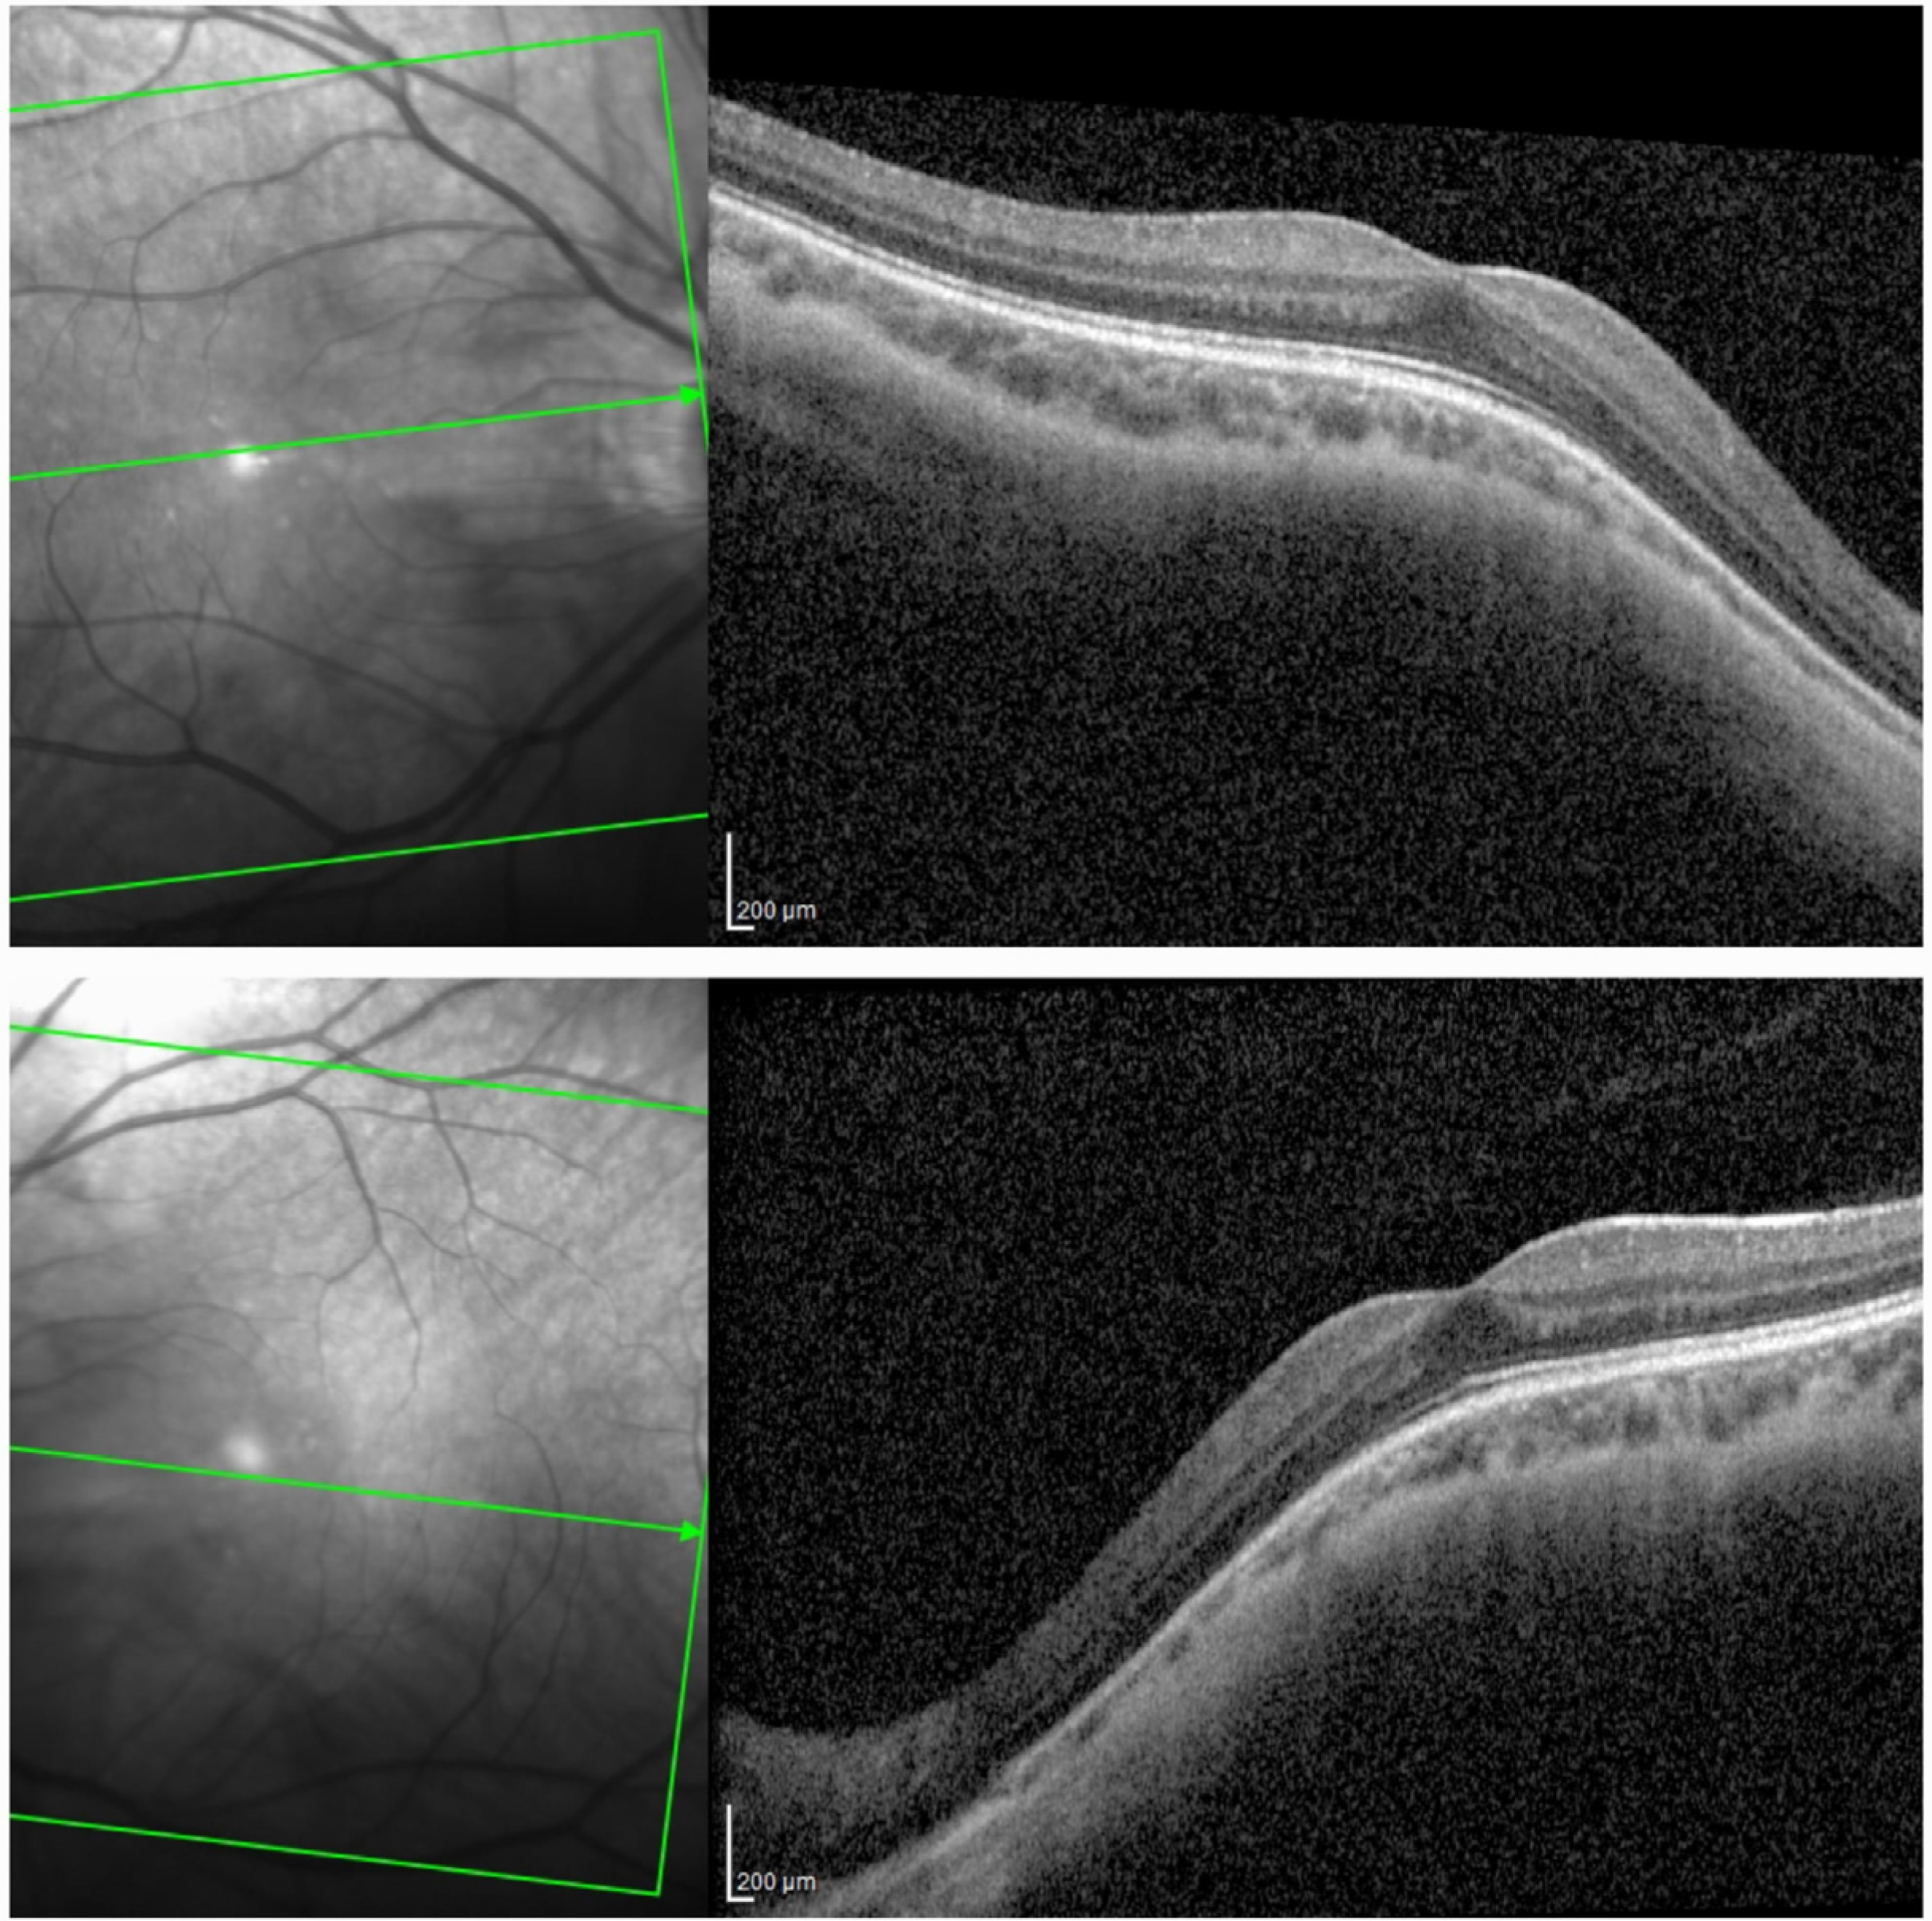

2. Case Presentation

2.1. Case Description